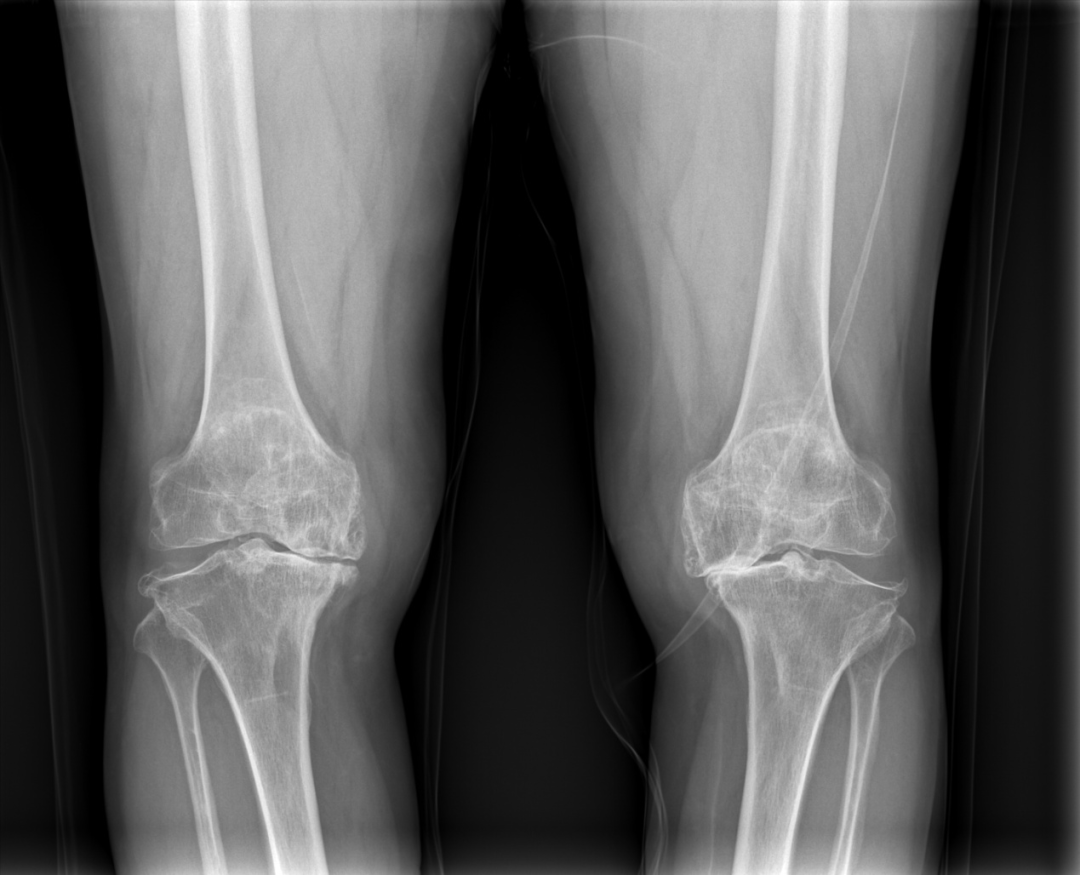

案例——66岁的蒲女士,10多年前因患有“类风湿性关节炎”,逐渐出现双膝关节活动受限、行走困难,随着病情日益加重,双膝关节疼痛让她寸步难行,多年的寻医问药,让她生活苦不堪言,2022年9月蒲女士慕名来到我院骨伤科徐驰主任门诊就诊。

术前双膝关节退变严重,关节间隙基本消失